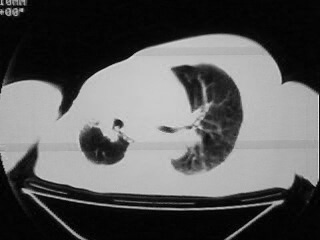

以下是引用随光逐影在2009-2-10 0:07:00的发言:[br]1)右肺放射性肺炎并节段性肺不张?请结合相关病史。2)右侧胸膜肥厚、粘连。3)心包膜增厚(或心包少量积液)。